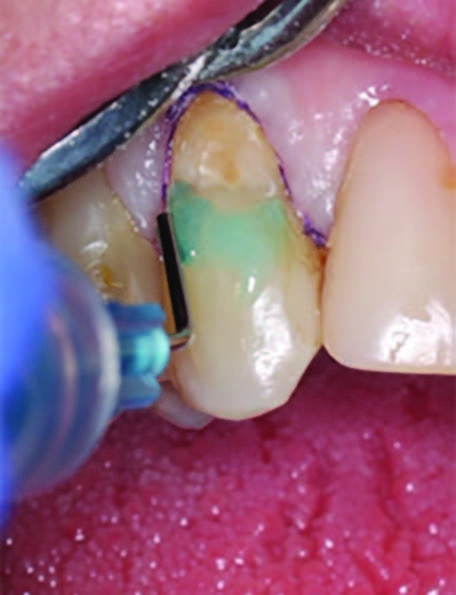

To improve isolation and soft tissue access, a retraction cord was placed before initiating the procedure (Fig. 2). The tooth was evaluated using a caries indicator dye (Kuraray Noritake Dental), helping to identify any remaining infected tissue beneath the dislodged composite (Fig. 3). Decay removal was completed with a diamond bur, and the enamel was bevelled using a starburst pattern to enhance aesthetic blending (Fig. 4). This preparation design was chosen for visual integration rather than bond strength enhancement.

Figure 2. Placement of the retraction cord to improve isolation and access to the cervical area prior to preparation.